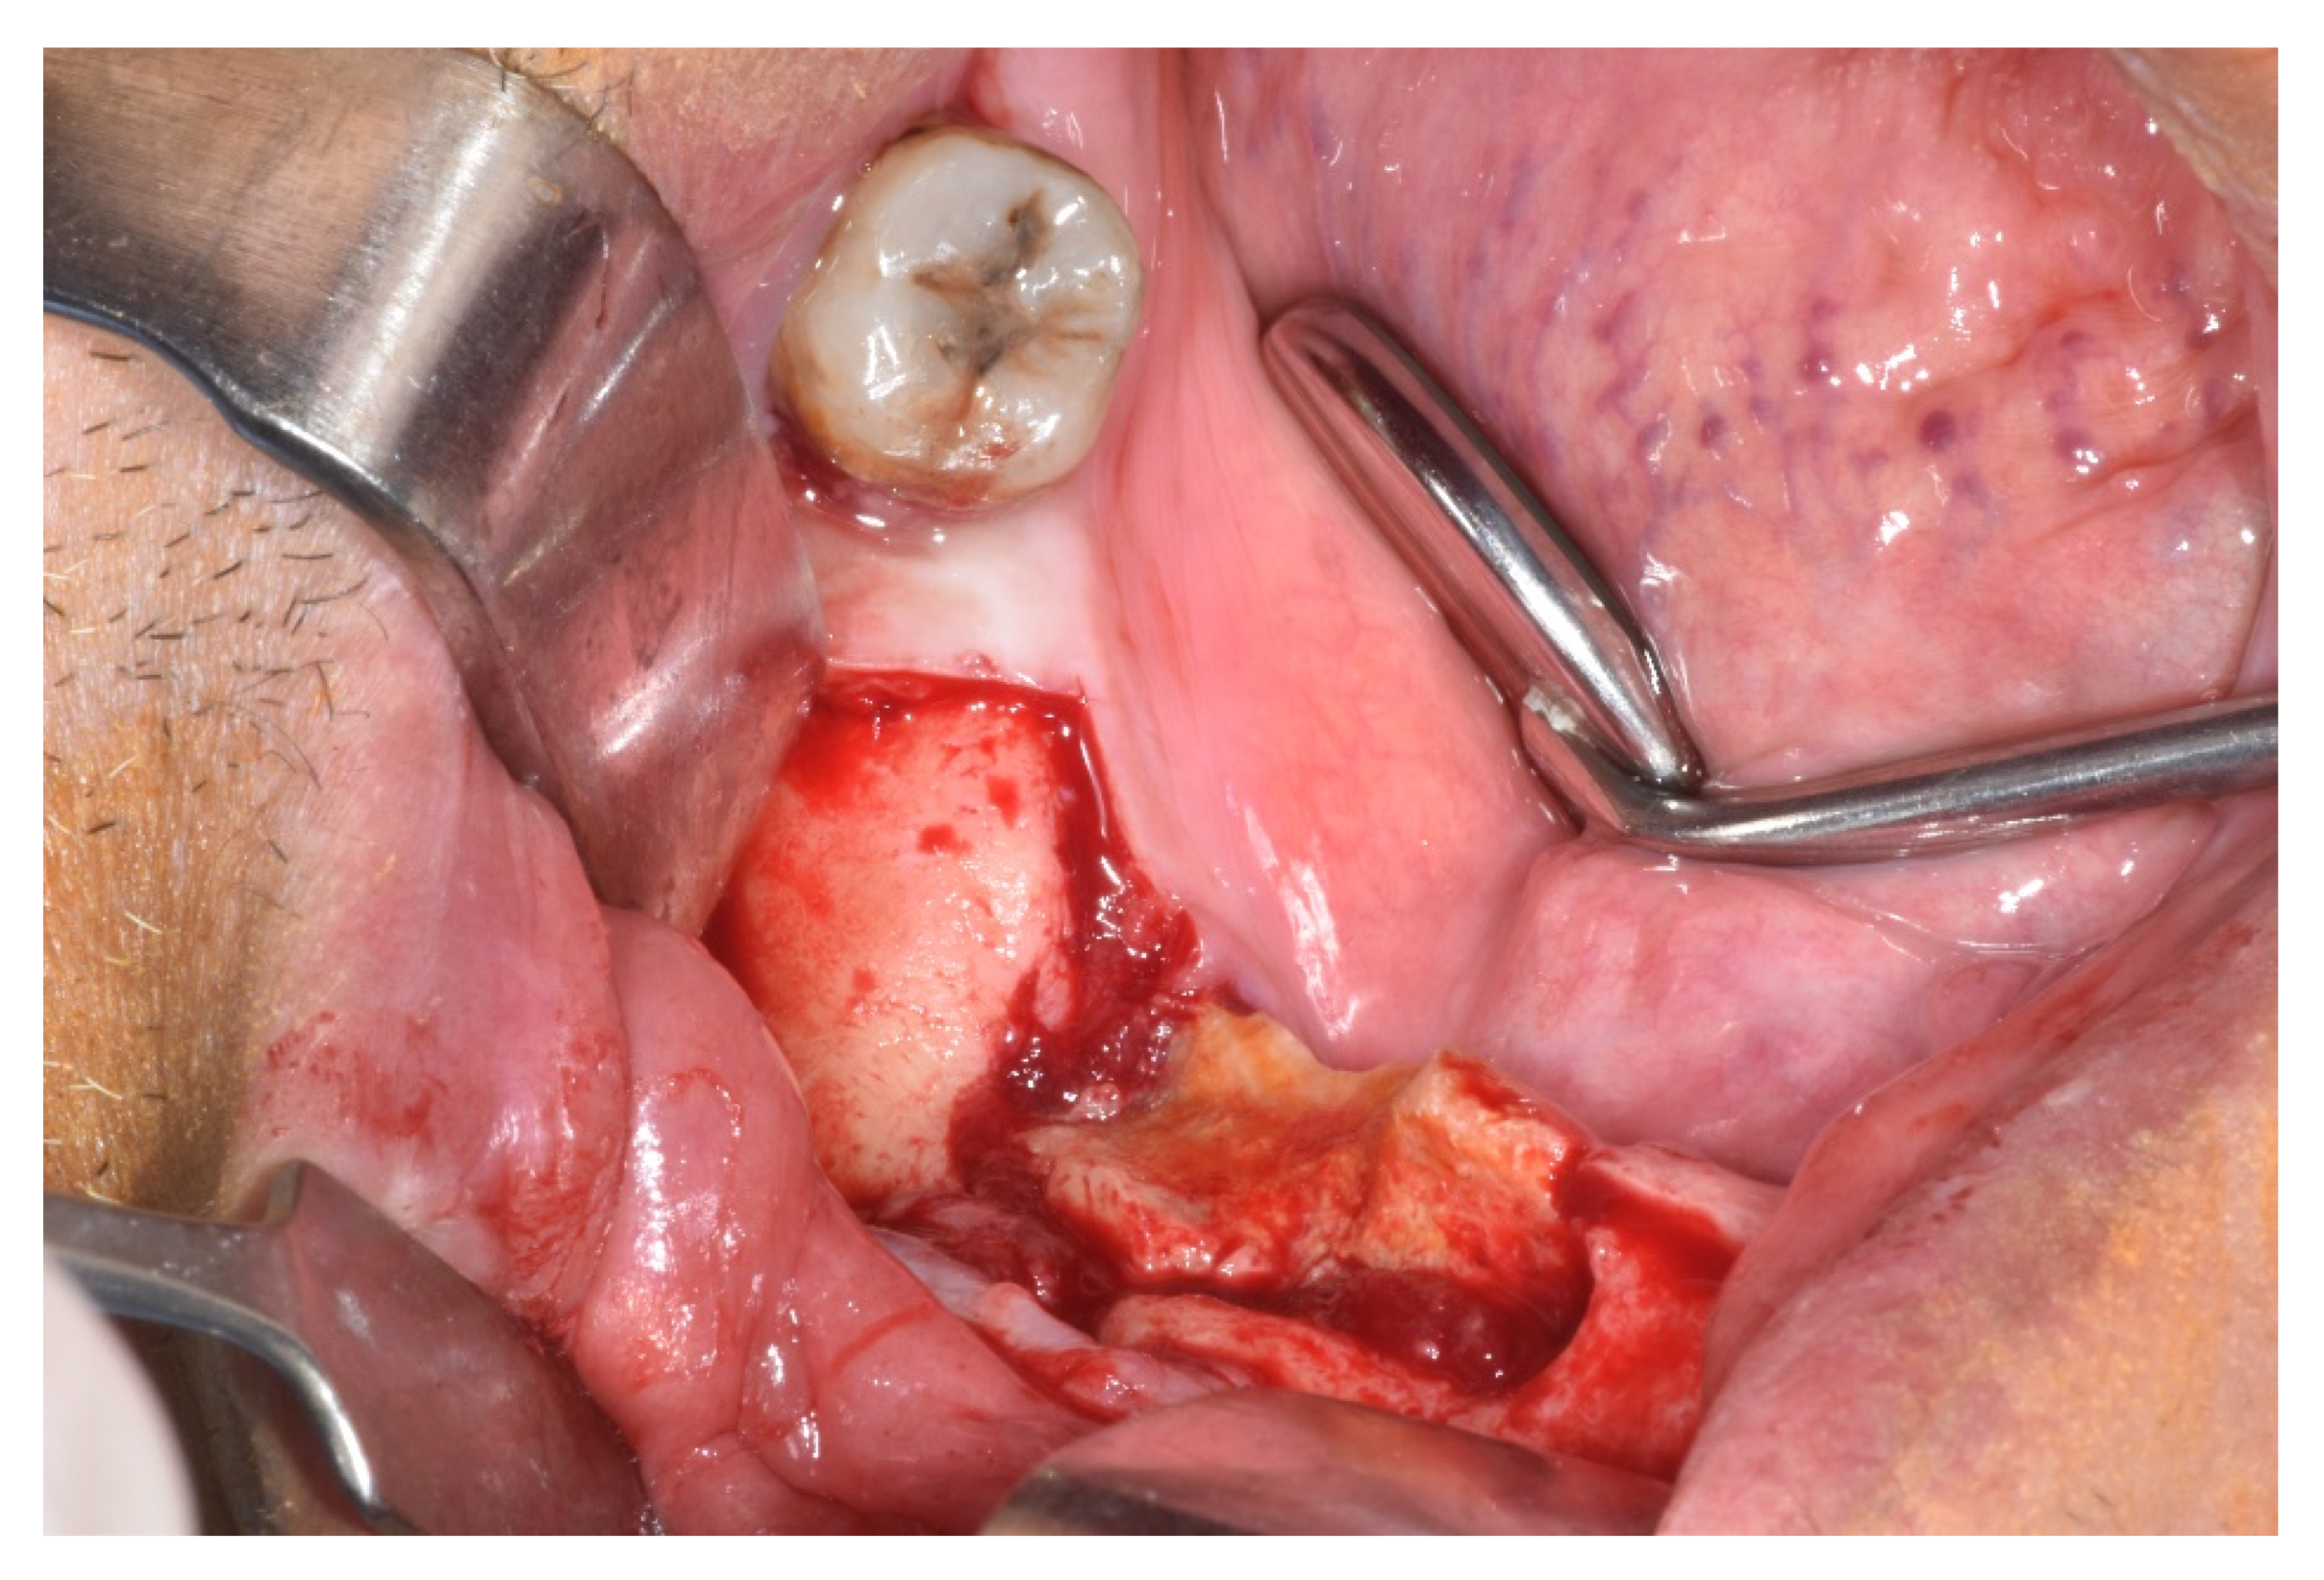

| Treatment | ||||||||

| Medical | x | x | x | 3 | 6 | |||

| Surgical | x | x | x | 3 | 10 | |||

| Procedure | ||||||||

| Debridement | 3 | |||||||

| Sequestrectomy | x | 1 | 1 | |||||

| Saucerization | 3 | |||||||

| Submarginal resection | x | x | 2 | 3 | ||||